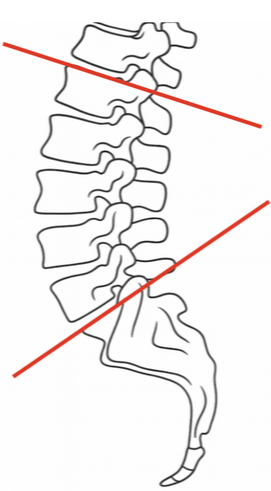

On a lateral lumbar X-ray, lumbar lordosis is typically measured by drawing lines along the superior endplates of L1 and S1, then erecting perpendiculars to each; the angle formed at their intersection is recorded as the lumbar lordosis angle.

Normal range: ~40°–60°

< 40°: Hypolordosis (can indicate flat back or postural imbalance)

> 60°: Hyperlordosis (seen in conditions like spondylolisthesis or postural compensations)